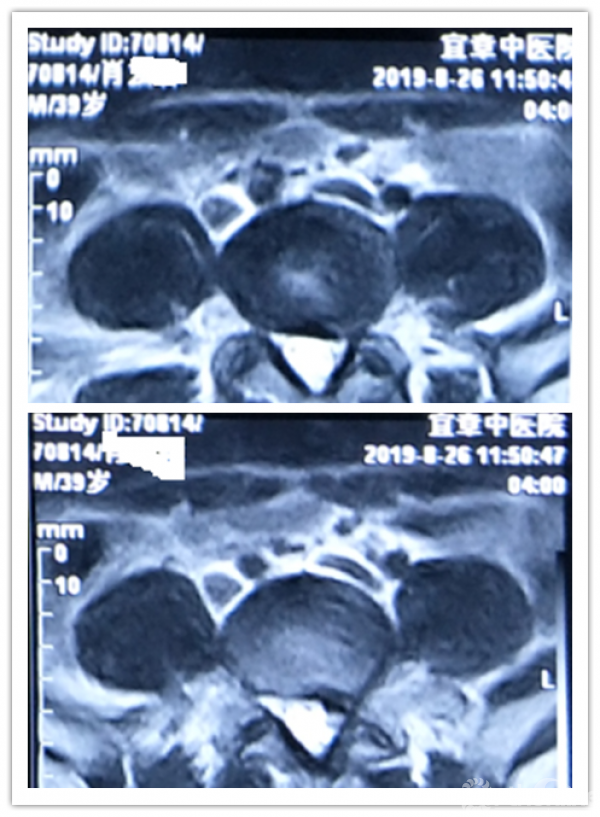

病程:腰痛伴左下肢放射痛5年,加重5天入院,入院诊断:L4/5椎间盘脱出伴坐骨神经痛。

MRI、CT影像学表现:

既往体健。专科情况:L4/5稍有压痛,左臀部致左下肢伴有明显放射胀痛感,以左小腿前外侧为明显;左侧直腿抬高试验(+),左侧踇背伸肌肌力IV级,左下肢伴有明显跛行,左侧膝反射减弱,余(-)。